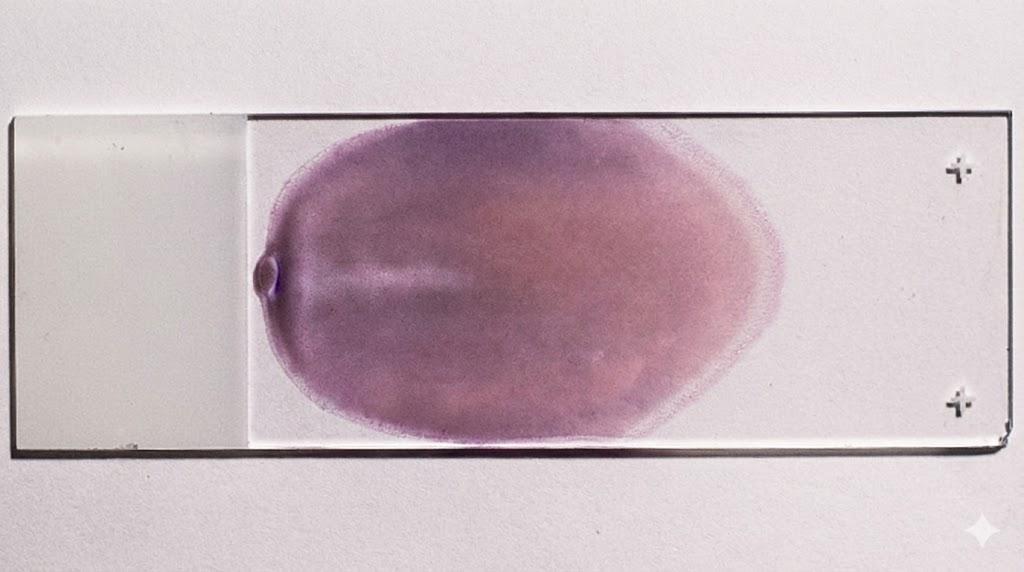

Below is an image of a peripheral blood smear.

This means that a clinical laboratory scientist took a drop of a patient's blood, skillfully smeared it to created a fanned out shape as shown in the image above, and then stained it with a special stain called the Wright-Giemsa stain.